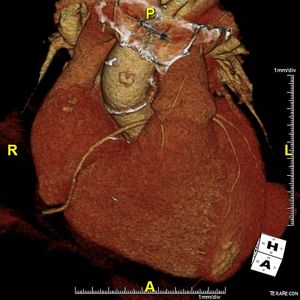

Image IQ: 74-year-old, History of Aortic Valve RepairByDuke Duncan, MDApril 17th 201574-year-old with history of aortic valve repair at an outside hospital.